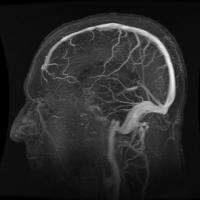

Brain Can Map Negative Spaces in the Body, Scientists Say

There is no doubt that the human brain is very powerful. In a recent study by the University of South Australia, scientists discovered that the brain has the ability to know which part of the body is healthy or neglected. The brain knows what area hurts Their findings were part of a research about the spatial perception of people with complex regional pa